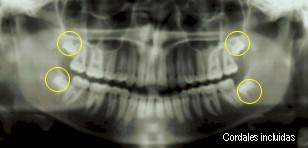

¿Por qué extraer las cordales y piezas incluidas?

A medida que el ser humano ha evolucionado, los arcos maxilares

disminuyen de tamaño por el tipo de alimentación, cruce de razas, etc.

Este proceso hace que en la actualidad no exista espacio para

la erupción de las cordales, por esta razón generalmente se encuentran en mala

posición o están incluidas; constituyéndose quistes en potencia,

lo cual es una razón para retirarlas.

Se ha demostrado con estudios que las muelas del juicio tienen

relación con casi todos los órganos del cuerpo.

Las cordales retenidas pueden producir tartamudez, epilepsia,

dolores articulares, de cabeza, problemas en el corazón, deficiencia de

calcio y calambres musculares, entre otros.

De igual manera las otras

piezas incluidas pueden ocasionar un desequilibrio de la fuerza vital, ya que

impide el flujo normal de la energía a través del meridiano poniendo en riesgo

su salud.